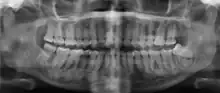

Florid osseous dysplasia of the mandible | |

Diagnostic method | X-ray, CBCT scan, vitality testing of teeth |

Cemento-osseous dysplasia (COD) is a benign condition of the jaws that may arise from the fibroblasts of the periodontal ligaments. It is most common in African-American females. The three types are periapical cemental dysplasia (common in those of African descent), focal cemento-osseous dysplasia (Caucasians), and florid cemento-osseous dysplasia (African descent). Periapical occurs most commonly in the mandibular anterior teeth while focal appears predominantly in the mandibular posterior teeth and florid in both maxilla and mandible in multiple quadrants.